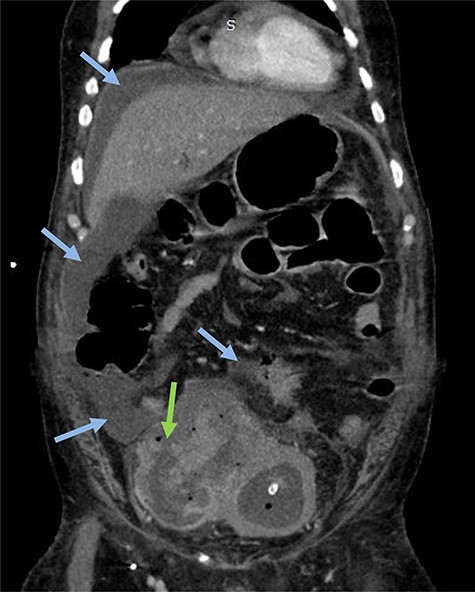

A 63-year-old man with a history of transurethral resection of prostate and a ballistic lithotripsy of bladder stone 15 years ago, presented with low urinary tract symptoms and hematuria. Cystoscopy showed multiple bladder stones and a bulky tumor mainly intradiverticular (Fig. 1). Partial resection of the tumor was done and pathology concluded on a squamous cell invasive bladder carcinoma. Since staging showed no metastatic lesion, a cystoprostatectomy was decided. Its execution was delayed because of a pulmonary embolism treated with curative anticoagulation and a severe paraneoplastic hypercalcemia treated with Zoledronic acid and veinous hydration on hospitalization. At Day 10 from admission and Day 60 after endoscopic resection of the tumor, the patient complained of abdominal pain, with diffuse tenderness and fever. Biology shows biologic inflammatory syndrome and kidney failure. Peritonitis was suspected and CT-scan showed a perforated bladder diverticulum with intraperitoneal effusion (Fig. 2). An emergency surgical investigation was executed, objecting a peritoneal cavity filled with nauseating hematic urine derived from a 2 cm disruption at the level of a posterolateral bladder diverticulum (Fig. 3). Radical cystectomy was performed. The patient was in severe septic shock requiring catecholamines and the procedure had to be shortened. No pelvic lymphadenectomy was done and bilateral ureterostomy was chosen as urinary diversion. The intervention lasted 2 h and there was no significant blood loss.

Emergency CT-scan showing intraperitoneal swallowing (blue arrows) due to a fistulization of the bladder (green arrow).